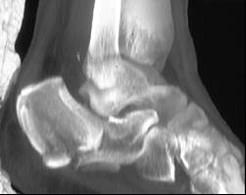

问题 男,34岁,从高处坠落后右脚跟剧痛,请结合影像学检查,选出最可能的诊断 ( )

选项 A、楔骨骨折 B、骰骨骨折 C、跟骨粉碎性骨折 D、舟状骨骨折 E、距骨骨折

答案 C